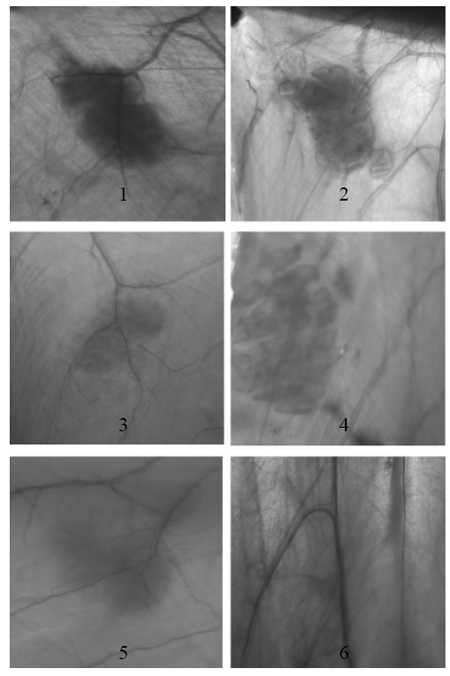

Рис. 1. Этапы имплантации мембраны из пчелиного воска в мышцы передней брюшной стенки 1) мембраны из пчелиного воска; 2) формирование кармана по размерам мембраны; 3) имплантация мембраны в формированный карман; 4) послойное зашивание раны

крысах средним весом до 150г. Животные были разделены на 2 группы: 1-контрольная, с созданием мышечного кармашка и 2-с эктопической имплантацией мембраны из пчелиного воска (МПВ). Под эфирным наркозом, тупым инструментом в косых мышцах пе-редней брюшной стенки создавался кармашек размером 1х0,5см, который соответствовал размеру МПВ (1х0,5см., толщиной 32-40мк) (рис. 1.2). У животных 1-ой группы кармашек оставляли пустым, а во 2-ой группе, в него имплантировали МПВ (рис. 1.3). Раны зашивались послойно, наглухо и обрабатывались 5% йодом (рис. 1.4). Животных выводили из опыта избыточной дозой эфира через 7, 15, 30, 60, 90, 120 и 180 суток. В эти сроки, изъятые после забоя животных тканевые блоки подвергались фиксации в 10% нейтральном растворе формалина и после проводки заливались в парафиновые блоки. Срезы, толщиной около 7-8мкм. окрашивались гематоксилин-эозином и пикрофуксином по ван Гизону.

На первые сутки и последующие сроки наблюдений за животными не было обнаружено каких- либо существенных нарушений сроков и процессов заживления ран после произведенного оперативного вмешательства. У всех животных послеоперационные раны зажили первичным натяжением. В срок наблюдения 7 суток. После обнажения косых мышц передней брюшной стенки животных, была заметна область проведенного вмешательства (рис. 2.1). При от-делении и просвечивании лампой передней брюшной стенки животных, у контрольной группы обнаружено затемнение в виде полнокровия с очагами крово-излияния, нарушение русел кровеносных сосудов в области вмешательства. У животных опытной группы четко можно было определить контуры мембраны из пчелиного воска (рис.3.1). В обеих группах, по соседству с зоной вмешательства, имело место некоторое снижение просвечиваемости передней брюшной стенки, что видимо обусловлено развивающимся послеоперационным отеком. Микроскопически регенерационно-грануляционные процессы выражены в контрольной группе реактивно-воспалительной реакцией с новообразованными сосудами, сформи-рованными либо путем почкования сохранившихся, либо без связи с имеющимися сосудами. Участки разволокнения мышечных волокон пронизаны плазматическими клетками и соединительной- грануляционной тканью, представленной полиморфными клетками от эндотелиальных, фибробласти- ческих, гистоцитарных до скопления нейтрофилов и макрофагов, а также сетью волокон, расположенных между сосудами (рис. 4.1). В препаратах опытной группы не обнаруживается макрофагальная реакция, имеющиеся соединительнотканные элементы в основном фибробластические, однако выявляются широкие просветы между мышечными пучками, указывающие на присутствие мембраны (рис. 5.1).

Наблюдения на 15-е сутки после операции мало отличались от результатов, полученных на 7-е сутки. Макроскопически имело место повышение про-зрачности передней брюшной стенки, исчезновение признаков отечности тканей. Область вмешательства у контрольной группы животных выглядела более прозрачной. В микропрепаратах отмечаются умеренные реактивно-воспалительные процессы с однотипными плотно расположенными одноядерными клетками и частично сохранившимися инфильтратами плазматического характера, присутствие тонкостенных сосудов капиллярного типа. Образование полос грубоволокнистой соединительной ткани в местах стыков разорванных волокон с упорядочиванием мышечных волокон (рис. 4.2). В опытной группе было заметно образование фиброзно-грануляционной ткани вокруг крупных вакулеобразных полостей (рис. 5.2). Последнее может свидетельствовать о начавшемся процессе биодеградации МПВ, которая фраг-ментируется на отдельные части и окутывается фи- бробластическими элементами.

На 30 сутки после имплантации мембраны в ложе. Макроскопически края мембраны стали более прозрачными и неровными, с мозаичной картиной (рис 3.2). Окружающие мембрану мышцы имеют строение, характерное для поперечно-полосатых мышц. Микроскопически прослеживалась гомогенизация поврежденных миофибрилл и пограничных участков мышц. Образование новых кровеносных сосудов и капилляров продолжалось (рис. 5.4). В гистограммах опытной группы количество фибробла- стов продолжало прогрессивно увеличиваться, наращивая зону грануляционной ткани, с уменьшением размеров пространств занятых мембраной. То есть, наблюдались процессы рассасывания МПВ и заме- шения этих участков фиброзно-ретикулярной тканью (рис. 5.4). Наблюдалось нарастание количества коллагенных волокон и формирование плотной грубоволокнистой соединительной ткани с развитой капиллярной сетью.

На 60 сутки после имплантации мембраны в мышечное ложе. Макроскопически область вмеша-тельства у контрольной группы была практически незаметна, почти полностью восстановилось сосудистое русло (рис. 2.2). В опытной группе животных мембрана напоминает картину мозаики с темными и более светлыми участками. Края мембраны неровные, зазубренные (рис. 3.4). Микроскопически местами отмечается инфильтрация сосудов с клеточными

Рис. 3 Макроскопическая картина области вмешательства в косых мышцах передней брюшной стенки живот-ных опытной групп (объяснение в тексте)

Рис. 4. Морфологическая картина области вмеша-тельства у животных контрольной группы (окраска гематоксилин-эозином, ув.х 60, объяснение в тексте)

Рис. 5. Морфологическая картина после эктопической имплантации мембраны из пчелиного воска (окраска гематоксилин-эозином, 1. 3. 4. 5. 6 ув.х 60, 2-ув.х 200 объяснение в тексте)

элементами, что подтверждает процесс ангиогенеза. Полости, занятые мембраной, различны по форме и размеру, окружены соединительной тканью с сосудами капиллярного типа, с коллагеновыми и эластическими волокнами, складывающимися в пучки.

Отсутствие соединительно-тканевой капсулы в зоне имплантации мембраны свидетельствует о био-совместимости материала. Все вышеописанные из-менения в области вмешательства у опытной группы животных можно оценить как результат активного рассасывания МПВ.

На 90-й день исследования зона вмешательства у контрольной группы животных макроскопически не определяется, полностью восстановилось сосудистое русло (рис. 2.3). В гистограммах лишь в некоторых препаратах прослеживаются линии спаек мышечных пучков (рис 4.3, 4.4). В опытной группе животных с имплантацией МПВ микроскопически примерно та же картина, что была описана на 60-й день исследования. Отмечается децентрация новообразованных волокон с сохранением микрополостей. Процесс формирования коллагеновых и эластических волокон активно продолжается, однако наблюдается уменьшение количества фибробластов и фиброгрануляционной ткани.

К четырех месячному сроку наблюдениий у жи-вотных опытной группы макроскопически заметны фрагменты мембраны, которые истончены, края зазубрены и неровны. В зоне вмешательства сосудистое русло практически восстановилось (рис. 3.5). Микроскопически заметно у опытной группы- неупорядоченное расположение мышечных волокон и местами сохранившиеся микрополости с неровными краями и с проникновением в них фиброзных тяжей и нежной сети соединительной ткани (рис. 5.5).

К концу эксперимента, на 180-ые сутки после оперативного вмешательства, у животных опытной группы наличие мембраны в мышечном ложе не на-блюдается, что свидетельствует о полном рассасывании мембраны. Сосудистое русло и прозрачность брюшной стенки были полностью восстановлены (рис. 3.6). Микроскопически во всех препаратах присутствовала восстановленная мышечная ткань с поперечной ориентацией волокон и сосудистой системой с участками сети фиброзной ткани, пронизанной грубоволокнистой с обрывками мышечных волокон (рис 5.6). Микроскопически заметны мышечные во-локна, нежная сеть фиброзной ткани, с участками грубоволокнистой ткани, которые свидетельствуют об окончательном формировании рубцовой ткани в области вмешательства.